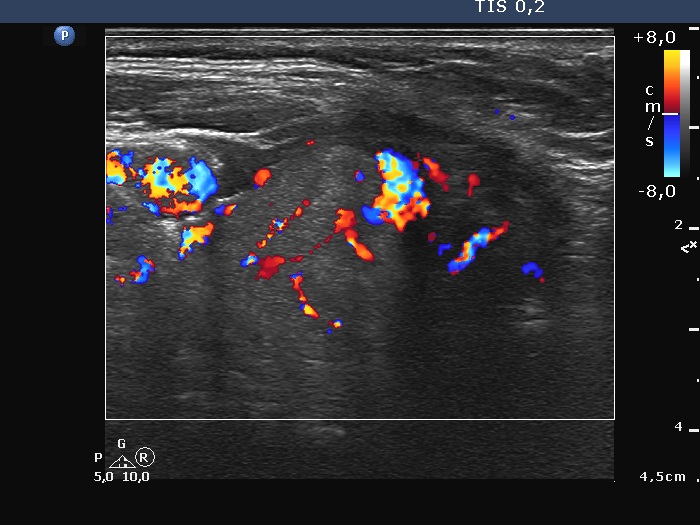

First examination (first row of images):

Ultrasonography. The thyroid was hypoechoic. There was a large, irregular, echonormal mass in the right lobe. The lesion presented both intranodular and perinodular vascularity. The left lobe was decreased in size.